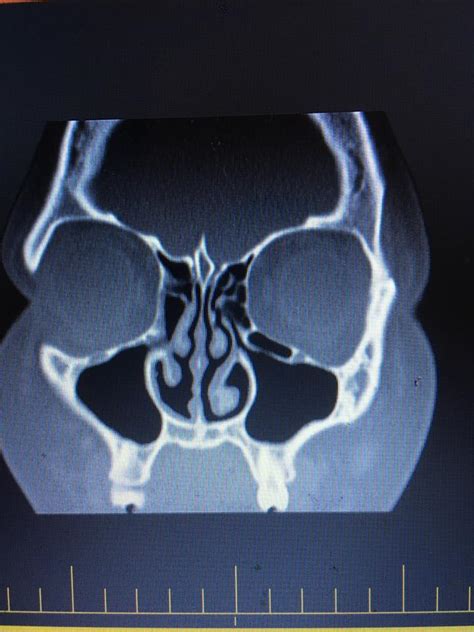

Okay, so why a CT scan and not just, say, a regular X-ray? Well, CT scans (computed tomography scans) give doctors a much more detailed look inside your body. Think of it like a super-powered X-ray. Instead of just one flat image, a CT scan takes multiple X-ray images from different angles and combines them to create cross-sectional views – like slices – of your sinuses. This allows the radiologist to see everything clearly. They can show the extent of the inflammation, see if there’s any fluid buildup (which is a big sign of infection), and even spot things like nasal polyps or structural problems that might be contributing to the issue. A CT scan is typically ordered when a doctor suspects that a patient has a chronic or severe sinus infection. This is because a CT scan is able to show fine details about the sinuses and surrounding tissues. If a person has a mild sinus infection, their doctor will most likely treat it by treating the symptoms. Sinusitis symptoms include: facial pain, a stuffy nose, congestion, headache, fever, cough, fatigue, and a reduced sense of smell. So, what do they look for on a CT scan ? Doctors will be looking at how inflamed the tissues are, if there are any blockages, and if there is a fluid build-up. The radiologist will be able to tell what may be causing your sinus infection, such as a bacteria or allergies. A CT scan of the sinuses can also detect complications such as orbital cellulitis (an infection of the tissues around the eye), meningitis (an infection of the membranes surrounding the brain and spinal cord), or a brain abscess. These complications are rare, but can be very dangerous.

So, what exactly are doctors looking for when they read a sinus CT scan ? The scan can reveal a variety of things, including:

• Inflammation: The most common finding is inflammation of the sinus lining. This looks like a thickening of the tissues within the sinuses.

• Fluid Buildup: This is a sign of infection and can appear as a dark area within the sinuses.

• Blockages: The scan can show if the sinus openings are blocked by swelling, mucus, or other obstructions.

• Nasal Polyps: These are small, noncancerous growths that can develop in the nasal passages or sinuses. The CT scan can help identify them.

• Structural Abnormalities: The scan can reveal any issues with the structure of your sinuses, such as a deviated septum (when the wall between your nostrils is shifted to one side). This can be a factor contributing to frequent sinus infections. The radiologist interprets these findings and provides a detailed report to your doctor. The report will describe what they see in the images and help the doctor make an accurate diagnosis and create a treatment plan. The doctor will most likely recommend treatments based on the results from the CT scan .